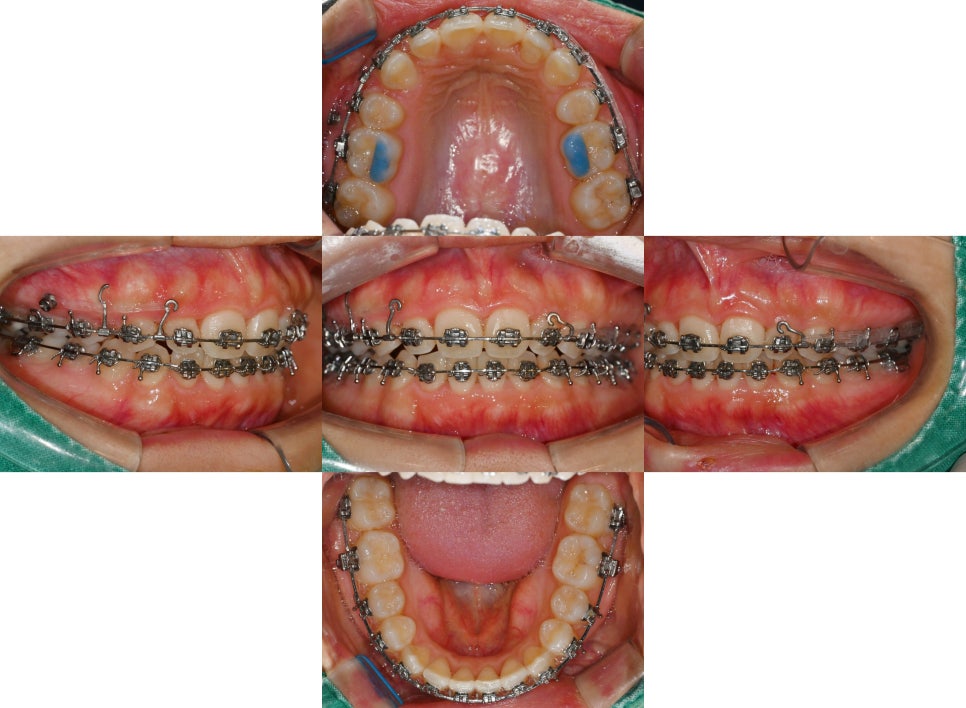

그런데 여기 사진을 보면 알 수 있듯이

양쪽 상악 소구치를 하나씩만 뽑는

‘편악발치’를 시행했음을 볼 수 있습니다.

편악 발치를 통해 위쪽의 14번과 24번을 뽑은 뒤,

치아를 이동시켜 조정하고 있는 모습을 볼 수 있습니다.

치료를 시작한 지 얼마 안 된 시점에서는

아직 유격이 존재해 다소 빈 느낌이 들지만,

서서히 치열 개선이 되면서 유격된 부분은 폐쇄됩니다.

그와 동시에 딥바이트에 관한 부분도

함께 개선을 해줍니다.

위아래의 교합 상태를 파악하고 어금니를 올려

전체적인 높이를 증가시켜 맞물림을 맞춰 나갑니다.